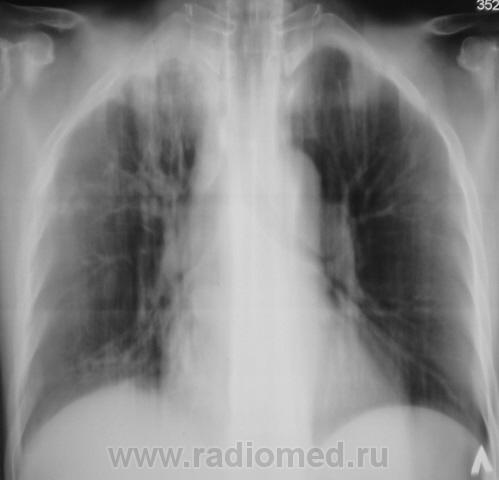

БОМЖ.

Контроль через 6 мес.